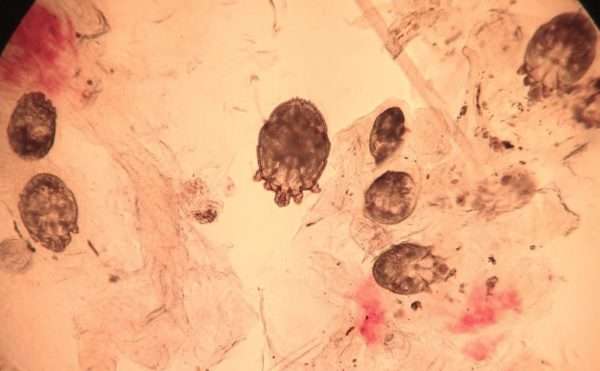

Это оптимальный способ лабораторной диагностики чесотки, поэтому используется чаще других. Анализ на скабиес заключается в получении биологического материала и последующего микроскопирования.

Перед забором биоматериала кожу пациента смачивают молочной кислотой или слабой щелочью, после чего клетки эпидермиса лучше отделяются. Дополнительно берут соскоб из-под ногтей больного.

Лабораторная экспресс-диагностика чесотки – новый метод исследования. Каплю 40% молочной кислоты наносят на возможный скабиозный элемент. Выдерживают 5 минут до разрыхления и соскребают поверхностный слой кожи, пока не появятся следы крови. Биоматериал перемещают на предметное стекло и сразу же микроскопируют.

При этом методе доктор получает для исследования взрослую особь клеща, доставая ее непосредственно из хода стерильной одноразовой иглой для инъекций. Под лупой туннель протыкают в месте, где видно затемнение. Предположительно это самка зудня.

Острие передвигают, клещ прикрепляется к нему. Его вытаскивают, помещают в воду или молочнокислую субстанцию и рассматривают под увеличением.

Тонкие срезы

Лезвием подчищают верхний пласт эпидермиса и обследуют его под окуляром. Предварительно кожу обрабатывают 5 минут каустической содой. Таким способом обнаруживают самих клещей, яйца, выделения, нимф.

Для подтверждения заражения человек должен пройти исследование соскоба. В процессе исследования снимают роговой слой кожи, которая повреждена сыпью, чесоточными ходами, папулами.

Благодаря соскобу можно обнаружить клеща, яйца или личинок паразита.

- роговой слой эпидермиса аккуратно снимают скальпелем или глазными ножницами, при этом захватывают папулы и везикулы,

- собранный материал изучается под микроскопом,

- подтверждением диагноза служат наличие личинок, яиц либо паразитов.